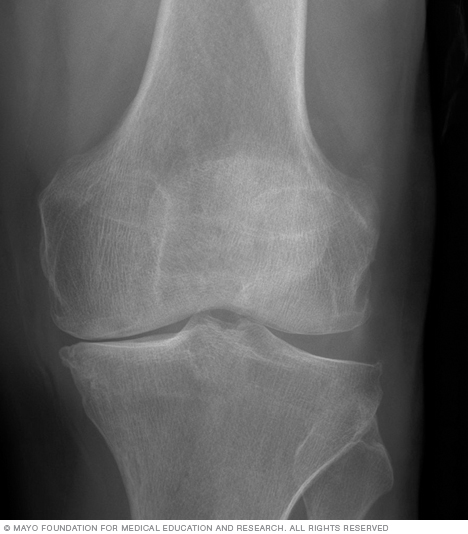

没有膝盖替代品没有年龄范围。这是一个减少功能和越来越匹配的痛苦,伴随着膝盖的X射线的痛苦。例如,如果你有50岁,有不良的关节炎,并且对你的生活质量不满意,那么它是合理的,经过全膝关节替代,以重新获得较年轻的年龄。

- 正在进行成像,因此您的外科医生拥有膝盖的最新照片。